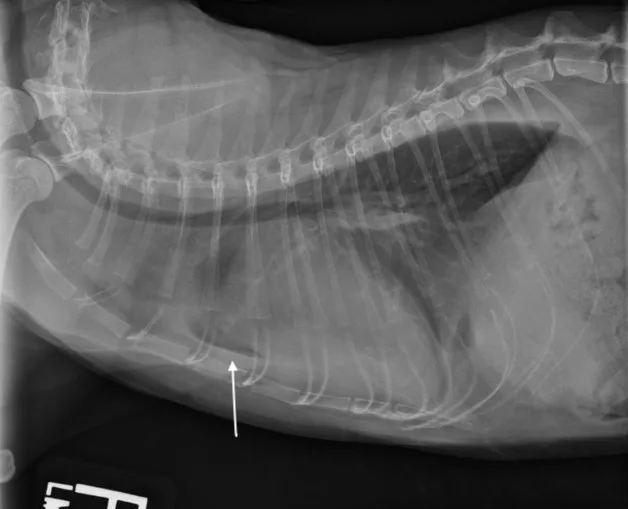

If clinical signs are not immediately life-threatening, at a minimum, a lateral thoracic radiograph should be obtained. Thoracic radiography is the gold standard for diagnosing pulmonary edema and venous congestion secondary to L-CHF.3,5 If the patient is not in distress, a 3-view study with a ventrodorsal or dorsoventral (VD/DV) view and opposite lateral thoracic views is ideal. Characteristic findings of cardiogenic pulmonary edema include increased interstitial-to-alveolar infiltrates of the perihilar and/or caudodorsal lung field in dogs.3,5 (See Figures 1A and 1B.)

FIGURE 1

(A) L-CHF in a Cavalier King Charles spaniel with mitral valve disease. Enlarged cranial lobar vessels are marked by the arrows. Enlarged left atrium is marked with an asterisk. (B) DV projection shows a caudal interstitial-to-alveolar pattern with air bronchograms (arrow). Images courtesy of University of Florida Small Animal Hospital

Left atrial enlargement is typically present in both cats and dogs with L-CHF. In dogs, left atrial enlargement typically appears in radiographs as a rounded increased opacity caudal to the carina in the perihilar region on the lateral projection. (See Figure 1A.) Generalized cardiomegaly is identified by measuring vertebral heart score (VHS).3,5 (See Figure 3.) In cats, both generalized cardiomegaly and left atrial enlargement are more difficult to assess because of their more subtle radiographic changes; they are characterized by a VHS score greater than 8 and the presence of a valentine-shaped heart on the VD/DV projection, respectively. However, normal left atrial size on thoracic radiography does not rule out the presence of L-CHF in dyspneic cats.1 Once acute L-CHF has been identified and treated, evaluation by a cardiologist is recommended, but stabilization of the patient is the first priority.